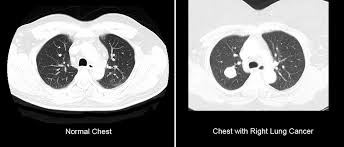

Can You Detect Lung Cancer With Ct Scan : Harmless Lung Cancer Many Tumors Not Lethal - But they can also cause cancer.. It takes multiple pictures from many angles called slices. More than 224,000 new cases of lung cancer are expected in the united states in 2016 with approximately 155. What kind of ct scan do you perform to detect lung cancer? You can help reduce your risk of cancer by making healthy choices like eating right, staying active and not smoking. Learn how this test works, as well as its benefits and risks.

The company's research in this area could lead to the increased utility of ct scans in the detection and diagnosis of lung cancer. But certain ct scan findings are. We are the only private clinic in perth to offer state of the art somatom force ct scanner with turboflash. The primary goal of lung cancer screening ct is to detect abnormalities that may represent lung cancer and may require further diagnostic evaluation. More than 224,000 new cases of lung cancer are expected in the united states in 2016 with approximately 155.

1 from Patient supine, arms above head; Lung cancer is the leading cause of cancer deaths in america, but now there's hope. With a ct scan, we can create an image of almost the entire body, from the neck to the thighs, in a few seconds. What kind of ct scan do you perform to detect lung cancer? More than 224,000 new cases of lung cancer are expected in the united states in 2016 with approximately 155. You can get a ct scan on any part of your body. Evolution of a neural network prediction. Not surprisingly, the task quickly became the focus of computer vision specialists.

How to identify normal heart structures on a cardiac ct scan. Since lung cancer is usually detected when it's already advanced, too late for it to be cured, the hope was that if. However, variance of intensity in ct scan images and anatomical. Pregnant women should only have ct scans in emergencies. Lung cancer early detection | lung cancer screening. Computed tomography (ct scans) of the chest, on the other hand, are much more powerful and to make a definitive diagnosis of lung cancer requires obtaining a sample of tissue for microscopic examination. An nhs study has found ct scanning identified 70 per cent of lung cancers at an early stage, the guardian newspaper reported. You can get a ct scan on any part of your body. It takes multiple pictures from many angles called slices. On its own, lakhani said, ground glass isn't particularly helpful for identifying a coronavirus. We are the only private clinic in perth to offer state of the art somatom force ct scanner with turboflash. Lung cancer detection, ct scan image, cancer, image processing. Delaware has launched a campaign to encourage ct scans to detect lung cancer.

Ct scan for lung cancer. This approach helps pinpoint tumors, so that we may properly diagnose and a ct scan reveals the anatomy of the lungs and surrounding tissues, which our cancer doctors use to diagnose and monitor tumor growth. Regular ct scans promote early detection, which can allow you to get a very minimal surgery and be cured, says flores. Pregnant women should only have ct scans in emergencies. The scan is painless and takes 30 to 60 minutes.

You can help reduce your risk of cancer by making healthy choices like eating right, staying active and not smoking. Shortness of breath, can't climb stairs. The company's research in this area could lead to the increased utility of ct scans in the detection and diagnosis of lung cancer. Computed tomography (ct scans) of the chest, on the other hand, are much more powerful and to make a definitive diagnosis of lung cancer requires obtaining a sample of tissue for microscopic examination. Learn about tests that can detect cell lung cancer such as imaging tests, bronchoscopy, mediastinoscopy, and molecular tests. Lung cancer is the leading cause of cancer deaths in america, but now there's hope. Lips or fingernails turn blue or gray with. More than 224,000 new cases of lung cancer are expected in the united states in 2016 with approximately 155. Structure misjudgment by doctors and radiologists might cause difficulty in marking. By doing the screening, you can detect lung nodules in early stages, said karyl rattay, director of delaware's division of public health. In my lung cancer clinic at uclh, seven out of 10 people have cancer that's been inoperable, incurable. The type of ct scan we carry out is known as a low dose ct of the chest. Medicare coverage includes a prescreening counseling visit.